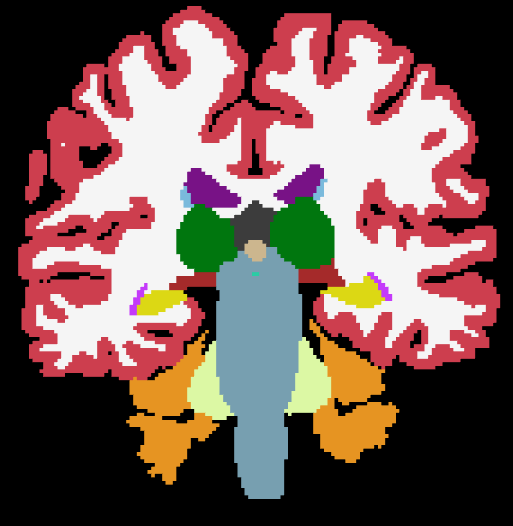

(a) MPRAGE

(b) SAMSEG

(c) MALF

(d) PSACNN

(e) T2-SPACE

(f) SAMSEG

(g) MALF

(h) PSACNN

In this experiment we use the same trained PSACNN network to segment co-registered MPRAGE and T2-SPACE acquisitions for 10 subjects that were acquired in the same imaging session. The acquisition details for both the sequences are as follows:

Figures 13(a)–(i) show the input MPRAGE and T2-SPACE images with their corresponding segmentations by SAMSEG, MALF, and PSACNN. ASEG and CNN are not built or trained for non--w images so we did not use them for comparison. We calculated the absolute relative volume difference of structures segmented for the T2-SPACE dataset with the same on the MPRAGE dataset. Table 3 shows the absolute relative volume difference for a subset of the structures. PSACNN shows the minimum absolute relative volume difference for six of the nine structures, with significantly better performance for subcortical structures including TH, CA, PU, and HI. SAMSEG has significantly lower volume difference for PA and LV. All algorithms shows a large volume difference for lateral ventricles (LV). The LV has a complex geometry with a long boundary and a segmentation one-two voxels inside or outside the LV of the MPRAGE image can cause a large relative volume difference. Synthetic T2-SPACE images generated in the PSACNN augmentation can match the overall image contrast with the real T2-SPACE images, however we believe the intensity gradient from white matter (dark) to CSF (very bright) is not accurately matched to the intensity gradient in the real, test T2-SPACE images, possibly due to resolution differences in the training and test data. This points to avenues of potential improvement in PSACNN augmentation. MALF (Fig. 13(c) and Fig. 13(g)) shows a diminished performance despite using a cross-modal registration metric like cross-correlation in the ANTS registration between the -w atlas images and the -w target images.

Since these two acquisitions were co-registered, we can calculate the Dice overlap between MPRAGE and T2-SPACE labeled structures, as shown in Table 4. As we can observe, PSACNN shows a significantly higher overlap than the next best method on six of the nine structures, and tying with SAMSEG for thalamus (TH). SAMSEG shows a significantly higher overlap for PA and LV.